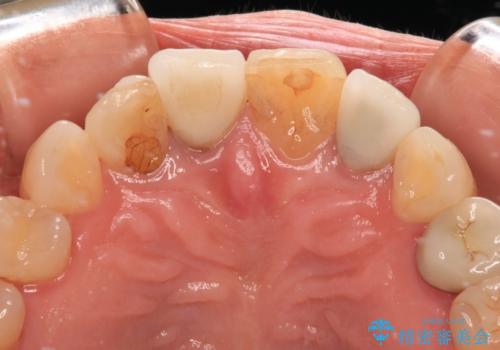

- 詰め物やクラウンで色合いが異なっている上顎前歯を気にして来院された患者様です。

長さや形を左右対称に整えたいとのことで、4歯をオールセラミッククラウンにて補綴治療を行うこととしました。